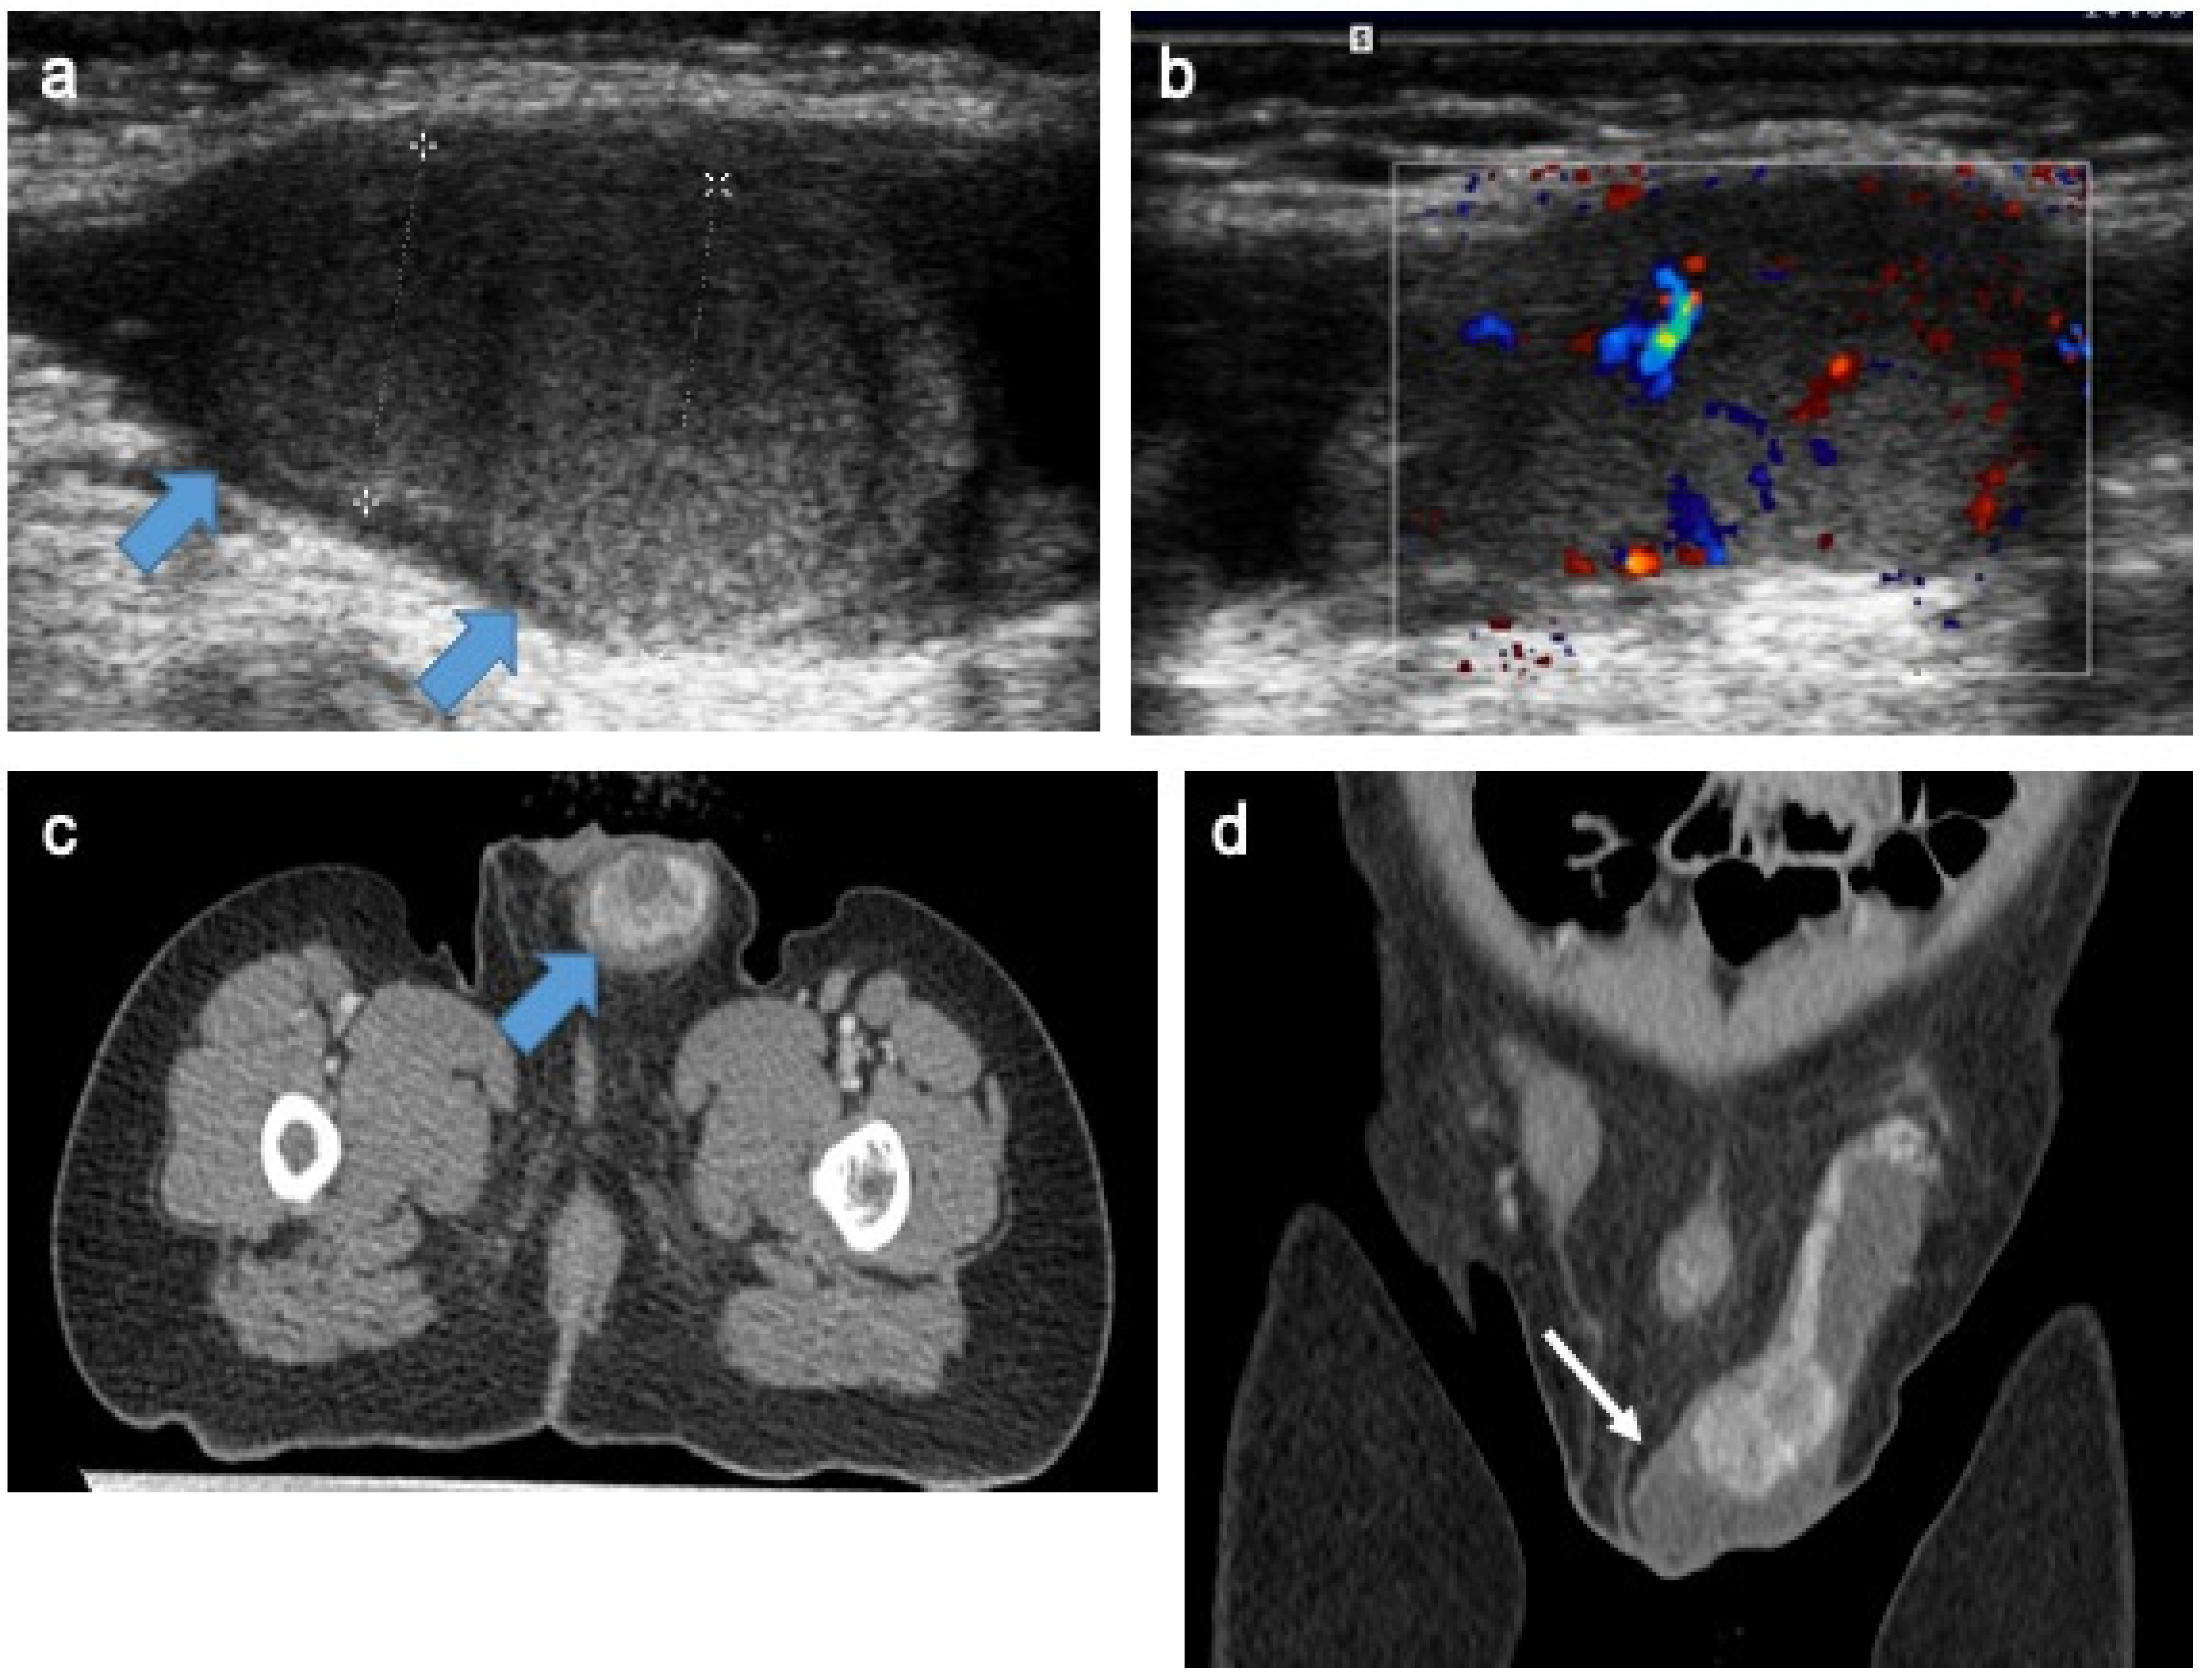

4.9. Testicular Adrenal Rest Tumors

- Yılmaz, R.; Şahin, D.; Aghayev, A.; Erol, O.B.; Poyrazoğlu, Ş.; Saka, N.; Yekeler, E. Sonography and Magnetic Resonance Imaging Characteristics of Testicular Adrenal Rest Tumors. Pol. J. Radiol. 2017, 82, 583–588. [Google Scholar] [CrossRef] [PubMed]

- Deshpande, S.S.; Shetty, D.; Saifi, S. Sonographic Appearance of Testicular Adrenal Rest Tumour in a Patient with Congenital Adrenal Hyperplasia. Pol. J. Radiol. 2017, 82, 526–529. [Google Scholar] [CrossRef] [PubMed]

- Mansoor, N.M.; Huang, D.Y.; Sidhu, P.S. Multiparametric ultrasound imaging characteristics of multiple testicular adrenal rest tumours in congenital adrenal hyperplasia. Ultrasound 2022, 30, 80–84. [Google Scholar] [CrossRef] [PubMed]